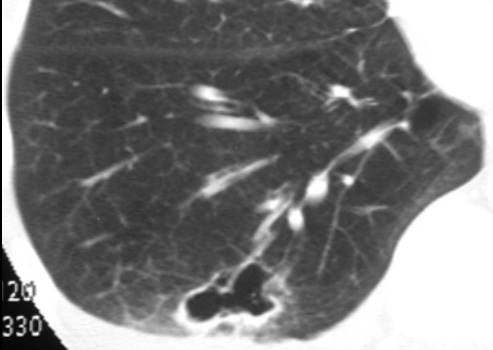

Cavitary Pulmonary Infarct

Surgically proven.